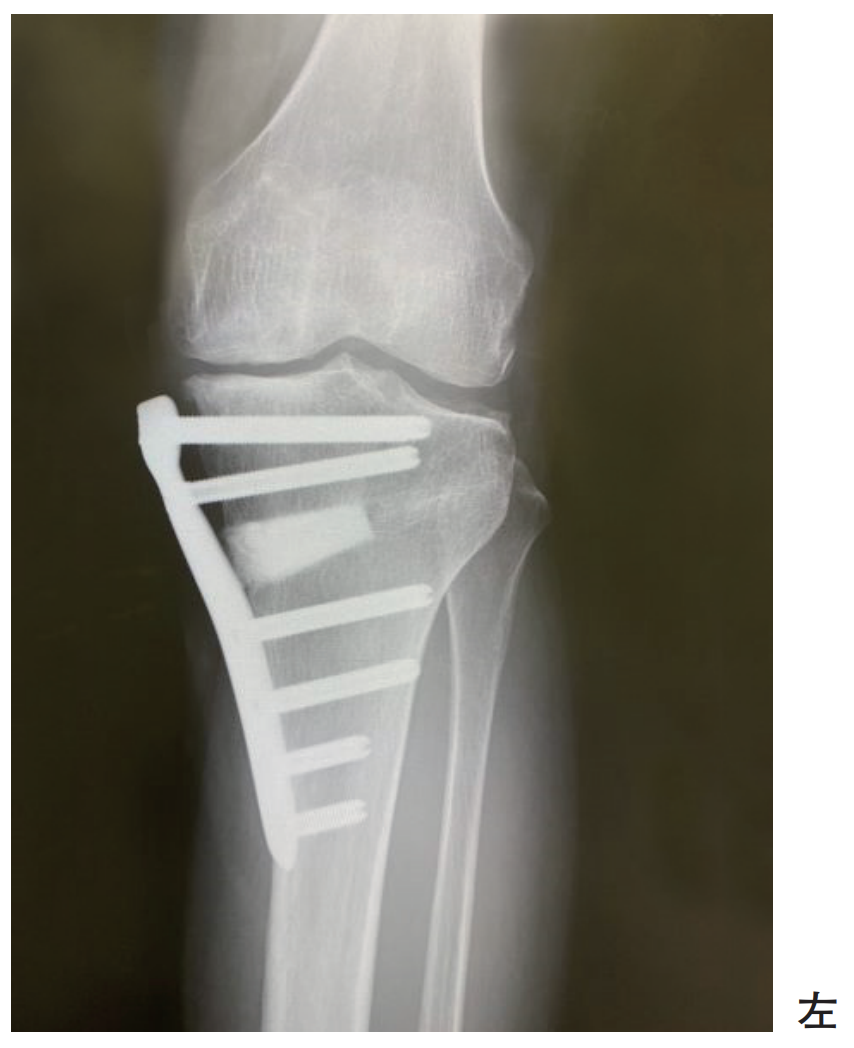

55歳の女性。趣味でジョギングを行っている。変形性膝関節症に対して手術療法が行われた。術後のエックス線写真を別に示す。

術後の理学療法で正しいのはどれか。